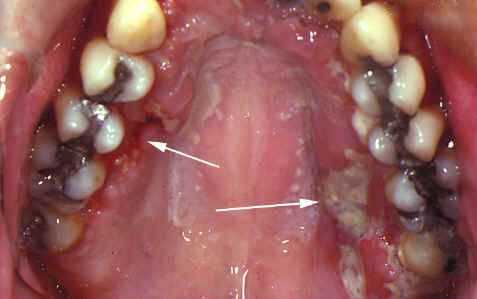

Данные осмотра полости рта: слизистая оболочка полости рта гиперемирована, умеренно увлажнена, галитоз. КПУ = 12 («К» = 5, «П» = 7, «У» = 0). Индекс гигиены по Green-Vermillion = 4 балла. Афты на правой и левой боковых поверхностях языка, округлой формы, размером соответственно 12х8 мм и 10х7 мм, афта на кончике языка диаметром 3 мм, афты на слизистой правой и левой щеки, размером соответственно 5 мм и 4 мм диаметра в поперечнике. Афты резко болезненны при дотрагивании, располагаются на гиперемированном основании, покрыты фибринозным налетом, который не снимается.

Диагноз: Рецидивирующий афтозный стоматит тяжелой степени тяжести. Афтоз Микулича.

Данные осмотра полости рта: слизистая оболочка полости рта бледно-розового цвета, умеренно увлажнена. Индекс гигиены по Green-Vermillion = 1,5 балла. Афты на правой и левой боковых поверхностях языка, округлой формы, размером соответственно 12х8 мм и 10х7 мм, видно начало эпителизации с краев афт, афта на кончике языка эпителизировалась, афты на слизистой правой и левой щеки, размером соответственно 3 мм и 2 мм диаметра в поперечнике. Афты умеренно болезненны при дотрагивании, располагаются на гиперемированном основании, покрыты фибринозным налетом, который не снимается.

Данные осмотра полости рта: слизистая оболочка полости рта бледно-розового цвета, умеренно увлажнена. Индекс гигиены по Green-Vermillion = 1,5 балла. Афты на правой и левой боковых поверхностях языка, размером соответственно 8х7 мм и 6х4 мм, на стадии эпителизации. Афты умеренно болезненны, располагаются на гиперемированном основании, покрыты фибринозным налетом, который не снимается. Афты на кончике языка, на слизистой правой и левой щеки эпителизировались. Явка через 2 дня с целью осмотра полости рта.

Данные осмотра полости рта: слизистая оболочка полости рта бледно-розового цвета, умеренно увлажнена. Индекс гигиены по Green-Vermillion = 1,5 балла. Афты на правой и левой боковых поверхностях языка, размером соответственно 3х2 мм и 2х2 мм, на стадии эпителизации. Афты умеренно болезненны, располагаются на гиперемированном основании, покрыты фибринозным налетом, который не снимается.

Данные осмотра полости рта: слизистая оболочка полости рта бледно-розового цвета, умеренно увлажнена, чистая. Индекс гигиены по Green-Vermillion = 1,5 балла. Афты на правой и левой боковых поверхностях языка эпителизировались. Явка через 2 дня, с целью осмотра полости рта.